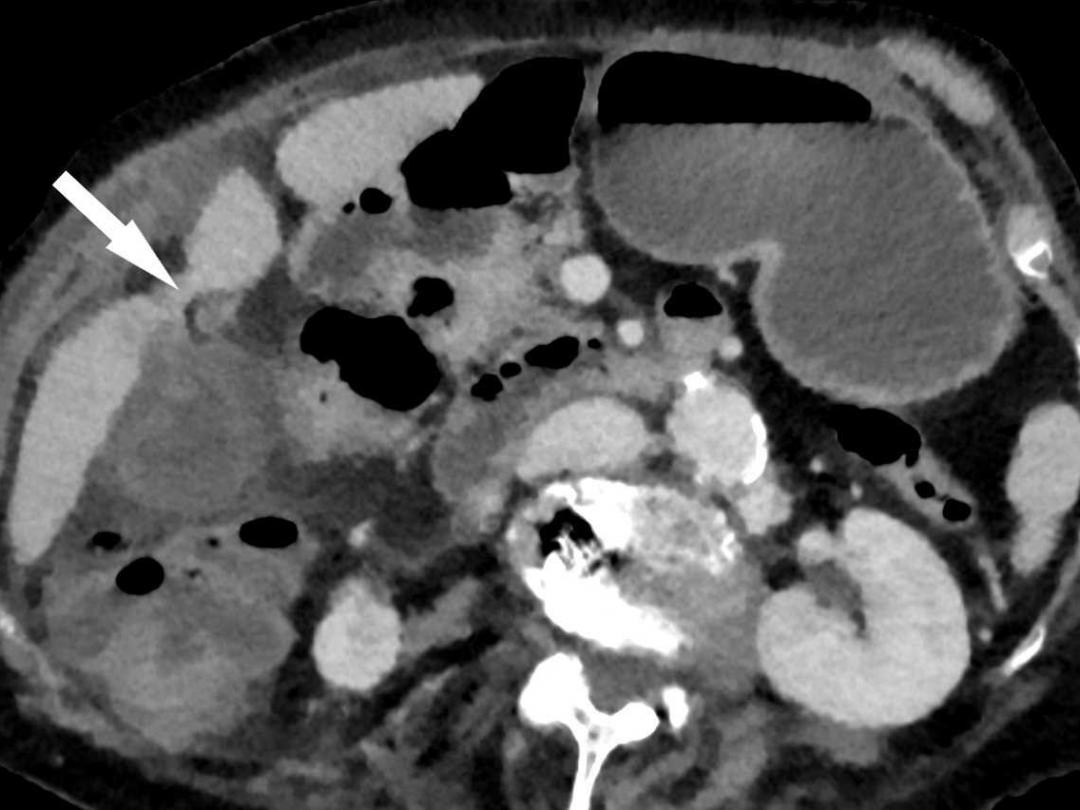

Een galblaastorsie is een zeer zeldzame aandoening waarbij de galblaas om haar lengteas is gedraaid. Klinisch lijkt een galblaastorsie sterk op een acute – acalculeuze – cholecystitis, waardoor het lastig is om de diagnose preoperatief te stellen.

Wij zagen een 81-jarige vrouw op de Spoedeisende Hulp met acute pijn in epigastrio sinds 3 dagen. De buikpijn had zich verplaatst naar rechts bovenin de buik en ging gepaard met braken. Wij stelden de diagnose ‘acute cholecystitis’ en gingen over tot een in opzet laparoscopische cholecystectomie. Hierbij kwam een getordeerde, necrotische galblaas à vue, waarna in tweede instantie de diagnose ‘galblaastorsie’ werd gesteld.

Peracuut ontstane buikpijn zonder duidelijke progressie in de tijd zou een reden moeten zijn om een galblaastorsie in de differentiaaldiagnose op te nemen. Dit symptoom in combinatie met de aanwezigheid van bepaalde risicofactoren en radiologische kenmerken vergroot ons inziens preoperatief de kans dat het om een galblaastorsie gaat.